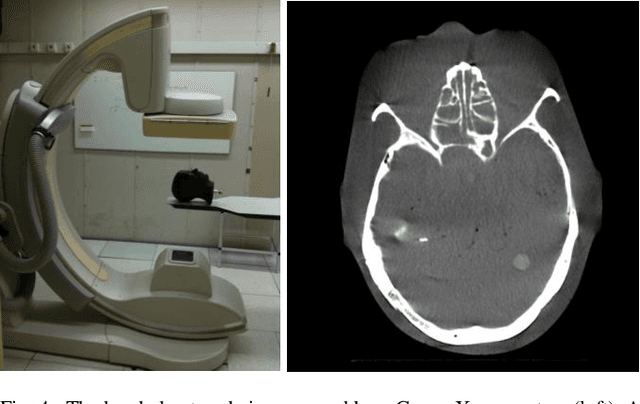

Fusing live fluoroscopy images with a 3D rotational reconstruction of the vasculature allows to navigate endovascular devices in minimally invasive neuro-vascular treatment, while reducing the usage of harmful iodine contrast medium. The alignment of the fluoroscopy images and the 3D reconstruction is initialized using the sensor information of the X-ray C-arm geometry. Patient motion is then corrected by an image-based registration algorithm, based on a gradient difference similarity measure using digital reconstructed radiographs of the 3D reconstruction. This algorithm does not require the vessels in the fluoroscopy image to be filled with iodine contrast agent, but rather relies on gradients in the image (bone structures, sinuses) as landmark features. This paper investigates the accuracy, robustness and computation time aspects of the image-based registration algorithm. Using phantom experiments 97% of the registration attempts passed the success criterion of a residual registration error of less than 1 mm translation and 3{\deg} rotation. The paper establishes a new method for validation of 2D-3D registration without requiring changes to the clinical workflow, such as attaching fiducial markers. As a consequence, this method can be retrospectively applied to pre-existing clinical data. For clinical data experiments, 87% of the registration attempts passed the criterion of a residual translational error of < 1 mm, and 84% possessed a rotational error of < 3{\deg}.